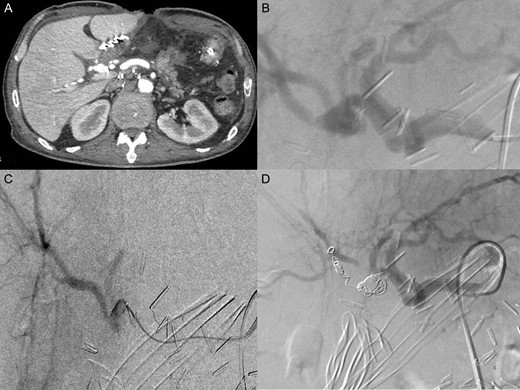

Post operatively, the patient was admitted to the ICU. First, he was under large doses of Noradrenaline. Three days later he was successfully extubated. No bleeding recurrence occurred. The patient had a CT scan with vascular reconstructions that showed an 11 mm pseudoaneurysm of the posterior branch of right hepatic artery with no signs of active bleeding. A multidisciplinary meeting with vascular surgeons and interventional radiologists decided to perform selective transcatheter arterial embolization (TAE) of the posterior branch of right hepatic artery. The TAE was done using micro coils type Terumo of various lengths and diameters (2 of 6 mm, 1 of 7 mm, 2 of 8 mm) (Fig. 2). Laboratory examinations at day 1 post TEA showed an increase of liver enzymes (ALT439UI/L, AST449UI/L) that trends to normalize afterwards. Control abdominal CT scan 3 days after TEA, showed signs of local ischemia of segment VI. The patient remained asymptomatic with normalization of liver enzymes. He was discharged home 6 weeks after surgery (Fig. 2).

(A) CT scanner arterial phase: pseudoaneurysm of posterior branch of the right hepatic artery (11 mm Ø) (B) celiac angiography showed pseudoaneurysm in posterior branch of right hepatic artery (C) selected microcatheter 2.8 F was coaxially advanced to the pseudoaneurysm (D) selected embolization with five micro coils type Terumo (two 6 mm Ø; one 7 mm Ø; two 8 mm Ø).